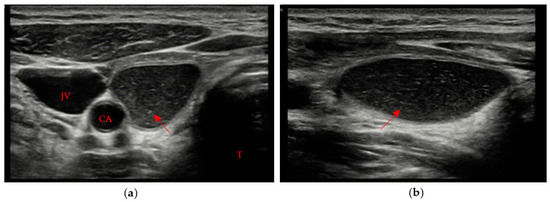

• A mildly hypoechoic or isoechoic pattern with ill-defined margins was found in 23 patients, which is approximately 58% of patients with evidence of residual swab (Figure 2a,b).

Figure 2. Residual swab pattern (red arrow) 2, characterized by a mildly hypoechoic/isoechoic ecostructure and ill-defined margins; (a) Longitudinal view; (b) Axial view. No vascular signal is seen at Color Doppler. Carotid artery (CA) and Trachea (T).